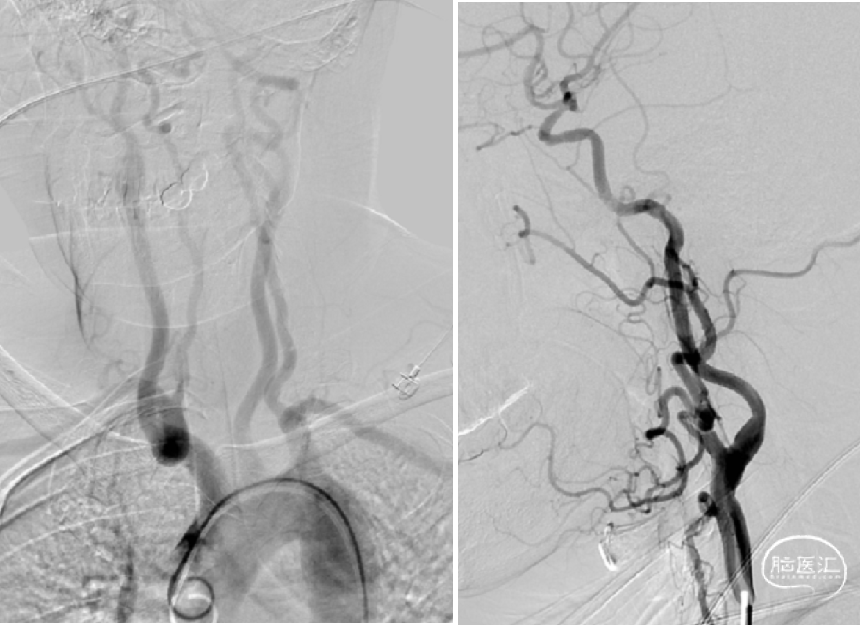

发病一周后完善了脑血管造影检查 。

正位

侧位

左侧大脑中动脉前向血流较同侧大脑前动脉缓慢。

3D:左侧颈内动脉C7段中度狭窄,左侧大脑中动脉M1段重度狭窄。